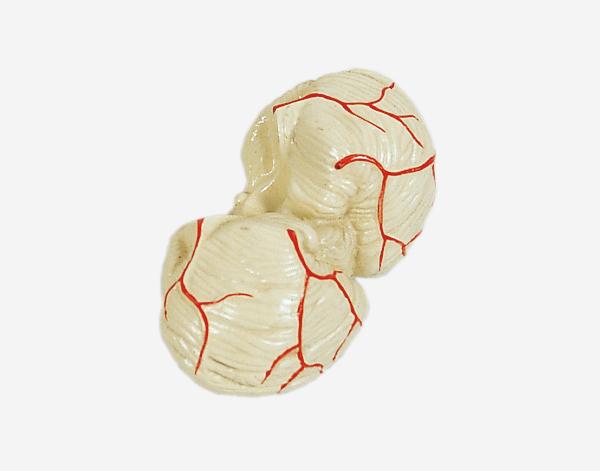

Human Brain With Arteries

Model of Human Brain With Arteries

This model facilitates the medical students to get a correct understanding of the external features of the brain and its arte

rial supply as a whole,as well as the relations between their component portions.External features of the brain:cerebral

hemisphere,brain stem,cerebellum.The arterial supply of the bra inaources,vertebral,internal carotid arteries,arteria supply of the

cerebellum and cerebrum.Made of PVC and can be separated into 7parts,on base.Size(cm):17x17x13